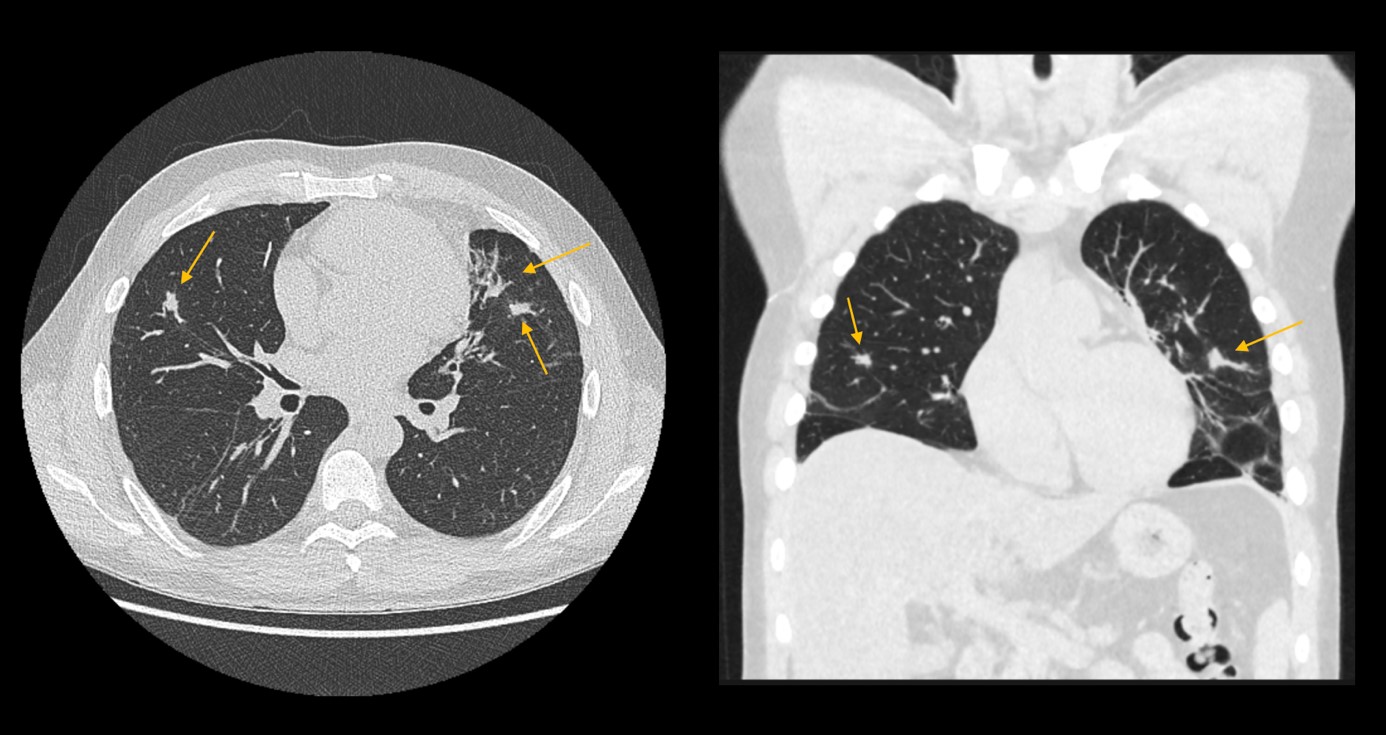

Kasus: 53-jähriger Patient mit bekanntem Asthma Bronchiale, Husten und Luftnot. In der Computertomographie zeigten sich multiple, dignitätsunklare bipulmonale Verdichtungen. Bei hochgradigem V.a. EGPA wurde auf eine Biopsie verzichtet. Eine Therapie mit Hochdosiskortison wurde eingeleitet. In der Verlaufskontrolle nach drei Monaten zeigten sich alle pulmonalen Herde weitgehend regredient.

Die Diagnose der EGPA basiert auf dem Vorhandensein bestimmter klinischer und laborchemischer Merkmale, darunter hohe Konzentrationen von eosinophilen Granulozyten. In 40% der Fälle werden pANCA nachgewiesen, in seltenen Fällen auch cANCA. Die Computertomographie spielt ebenfalls eine wichtige Rolle, um andere Ursachen für die pulmonalen Beschwerden auszuschließen. Es gibt keine pathognomonischen Lungenbefunde für die EGPA. Milchglasartige bipulmonale Verdichtungen wurden jedoch häufig beschrieben.